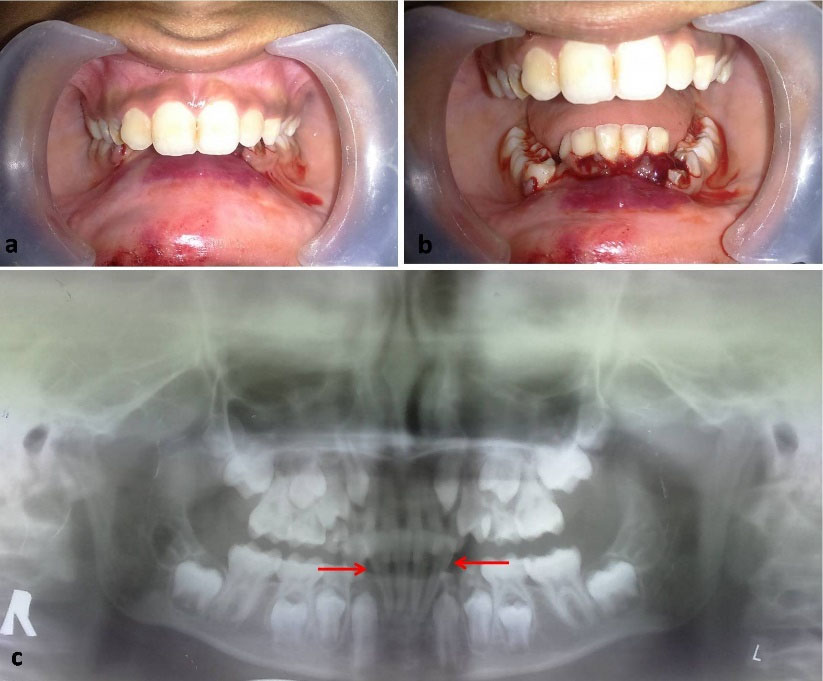

A 12-year-old boy was referred to the oral and maxillofacial surgery clinic with a chief complaint of bleeding from the mouth as a result of a fall from a bicycle. The patient reported on the same day of the injury and received immediate attention. The child was conscious and cooperative at the time of examination with vital signs within the normal limits. There was no history of loss of consciousness, bleeding from the nose and ears, vomiting, or convulsions. On the extraoral examination, the patient presented a normal (straight) facial profile with swelling over the lower lip and chin. Intraoral examination showed labial ecchymosis in the mandibular anterior region and a step deformity between the distal aspect of #32 and the distal aspect of #83. The anterior dentoalveolar segment was displaced superiorly and lingually, causing a deep bite (Figure 1a and 1b). The panoramic radiograph revealed a superiorly displaced dentoalveolar segment of the anterior mandible, confirming a diagnosis of dentoalveolar fracture (Figure 1c).

Figure 1.

Clinical presentation showing deep bite (a), and displaced mandibular anterior dentoalveolar segment associated with labial echymosis (b). Panoramic radiograph showing the fracture segment (c).